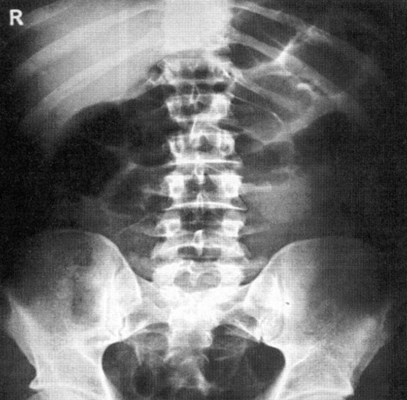

Информативность снимка. На обзорной рентгенограмме (электро-рентгенограмме) живота отображаются очертания печени, почек, больших поясничных мышц, желудка и кишечника (при наличии в них газа), а также диафрагма, вход в малый таз и боковые каналы брюшной полости (рис. 538).

На обзорных снимках живота, выполненных в положении больного стоя или сидя, хорошо видны раздутые газом кишечные петли с уровнями жидкости при кишечной непроходимости

На правильно выполненном снимке должны быть хорошо видны очертания паренхиматозных органов живота, диафрагма, нижние ребра, проксимальные отделы подвздошных костей и боковые отделы брюшной полости.

Позвоночник при симметричной укладке и отсутствии сколиоза располагается по средней линии снимка.